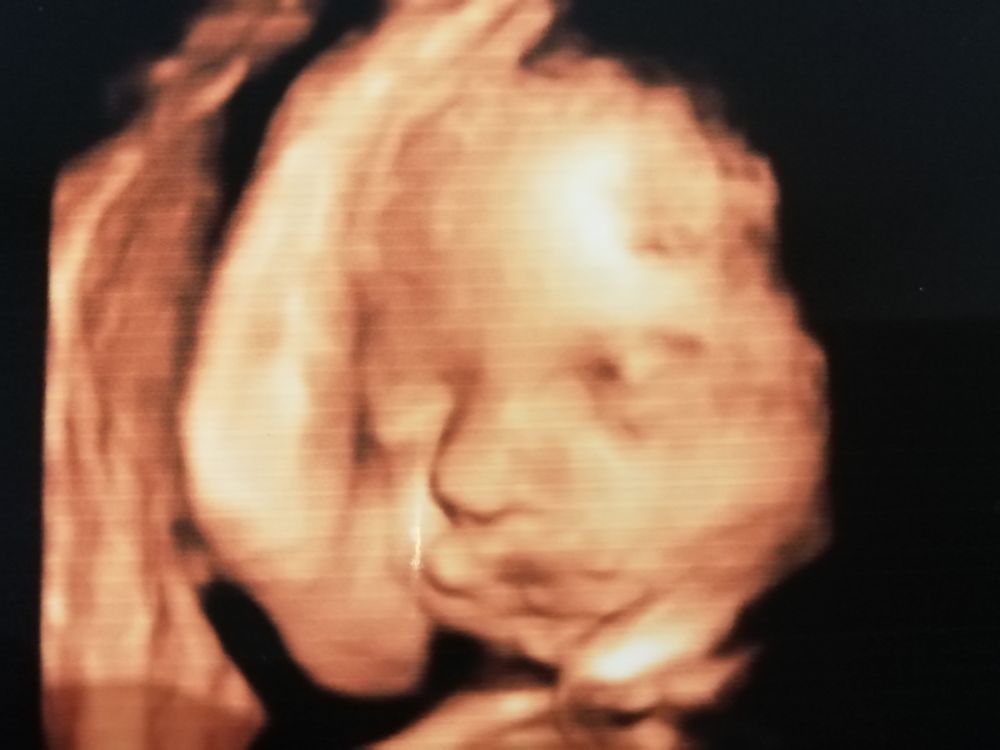

Довольна 3д узи. Хорошие снимки.

Я поняла что все зависит от врача. Приехала в ту же клинику где была в 17 недель, врач другой, отношение другое, фото мне глянцевых повыводили рассказали показали облизали, мы довольны!

Малыш в тазовом, но у меня будет пкс. Голова сказали большая. Весит 1,2 кг ровно. Завтра 28 недель.

Малыш что на прошлом узи руки задрал, что сейчас. Держит над головой. Нос мужа, да и вообще на меня не похож. У меня нос острый, щёк нет, а у мужа есть. Он горд и доволен.